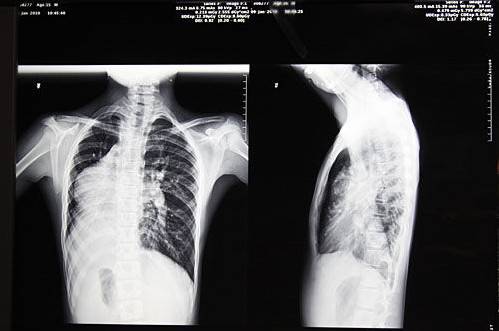

“镜面人”(Situs inversus),又称“镜子人”或“镜像人”,即心脏、肝脏、脾脏、胆等器官的位置与正常人相反。医学上对“镜面人”现象的成因还没科学定论。医学专家认为“镜面人”是在人体胚胎发育过程中出现突变有关,发生几率大约为百万分之一。